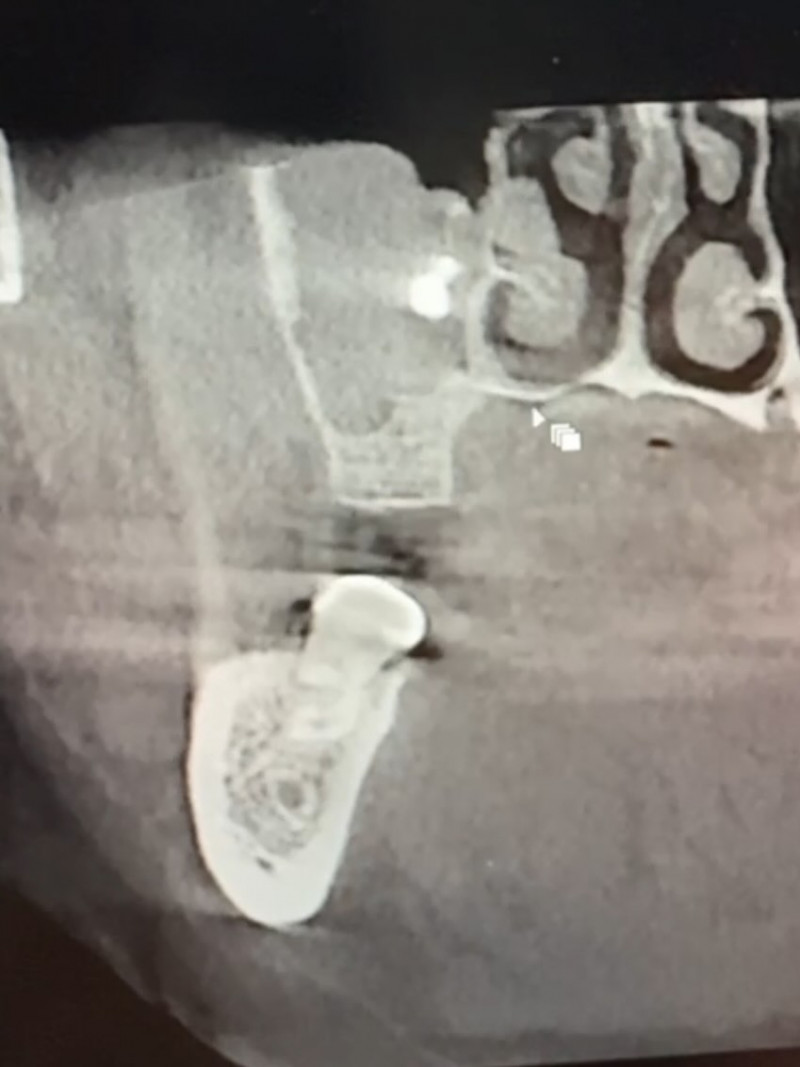

Медики Володимирського ТМО на Волині успішно видалили стороннє тіло у верхньощелепній пазусі.

Стороннє тіло було діагностовано під час прийому у стоматолога, повідомляють у медзакладі.

Після направлення до Володимирського ТМО лікарі-отоларингологи оперативно та успішно видалили стороннє тіло. Процедуру проведено без ускладнень, пацієнт почувається задовільно.

У подібних випадках при несвоєчасному зверненні можуть розвиватися гайморит, запальні процеси, біль, набряк обличчя або підвищення температури тіла.